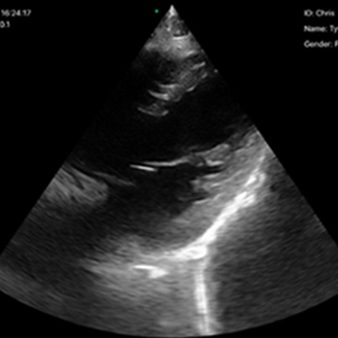

El escáner de ultrasonido portátil de doble sonda es una solución avanzada diseñada para ofrecer máxima versatilidad clínica en un solo dispositivo. Gracias a su tecnología integrada, combina tres modos de escaneo —convexo, lineal y phased array— permitiendo evaluar estructuras profundas, tejidos superficiales y realizar estudios cardíacos con alta precisión. Esta integración reduce significativamente los costos al reemplazar la necesidad de adquirir múltiples sondas por separado.

- Un solo escáner escanea todo el cuerpo, incluso el cardíaco.

Aplicaciones

Cardíaco